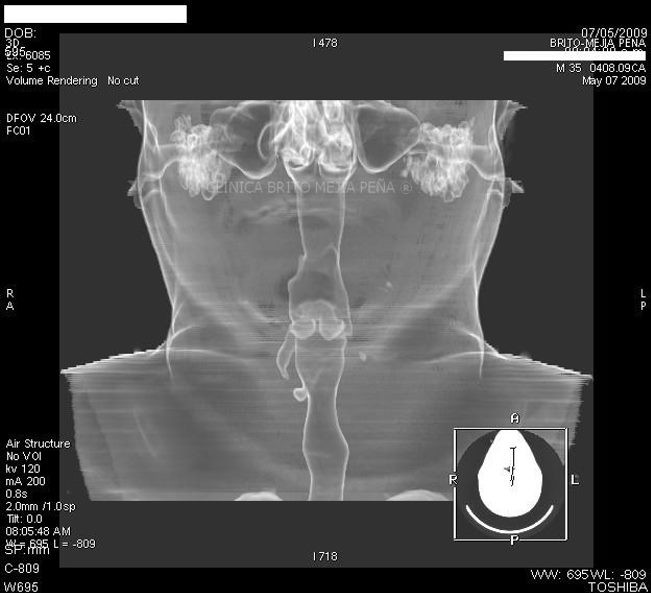

Espina en espacio retrofaríngeo